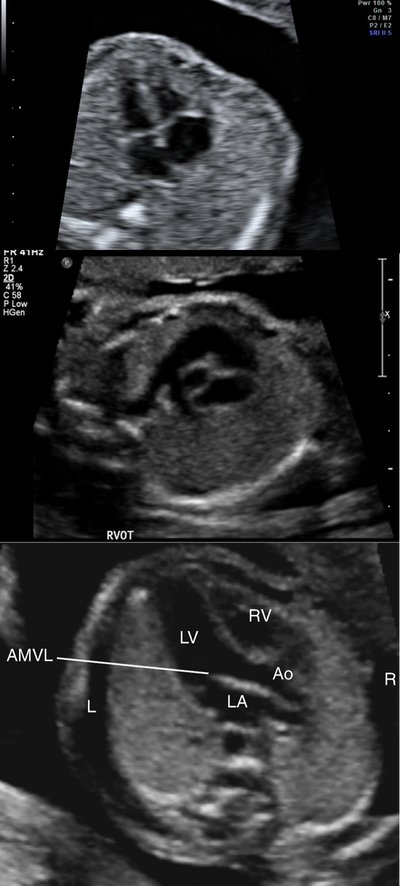

Prenatal identification and management of cardiac abnormalities are important since they are the leading cause of infant death and congenital heart disease accounts for 30 to 50% of these deaths.

Fetal echo is recommended for women with family history or previous child born with cardiac anomalies or if there is raised nuchal translucency measurement in the first trimester. Fetal echo is also recommended if other fetal anomalies are seen in routine or anomaly scan.

We at Chennai fetal care include careful assessment of fetal heart as part of the anomaly scan assessment. It’s important to be aware that fetal echocardiography is done to exclude major structural abnormalities in the heart that could alter the outcome of the pregnancy. Minor anatomical variants such as a small hole in the heart muscle (ventricular septal defect) is not always possible to be picked up on routine screening and may only be diagnosed after birth.

Once a complex cardiac abnormality is identified, the couple are counselled regarding the scan findings and the management pathway is discussed. We can also arrange a formal consultation with a specialist paediatric cardiologist / cardiac surgeon if necessary to discuss the management after birth.

Specialised fetal echocardiography would take approximately 30-45 minutes to perform and the scan findings will be discussed with the patient after the scan for further management. A copy of the report will also be sent to the referring Doctor with suggested management plan and follow up.